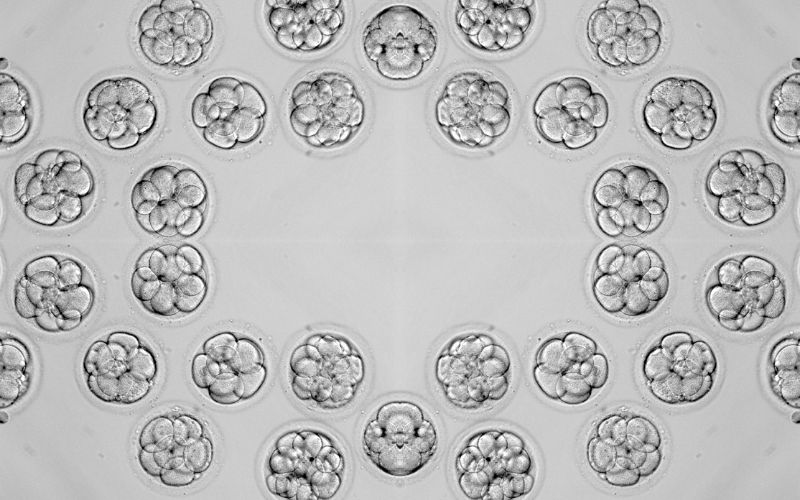

¿Cómo se clasifican los embriones? Tipos de embriones y diferencias

La clasificación embrionaria, distinguiendo entre los tipos A, B, C y D, es fundamental en los tratamientos de reproducción asistida. Establecer una diferenciación sirve para conocer la calidad y el potencial de cada embrión para desarrollarse tras la transferencia al útero, pero también orienta a los especialistas de las clínicas de fertilidad en su elección para aumentar las posibilidades de lograr un embarazo exitoso. La importancia de seleccionar los embriones de mejor calidad (Tipo A o B) radica en su mayor probabilidad de implantación, mientras que los tipos C y D presentan desafíos adicionales.